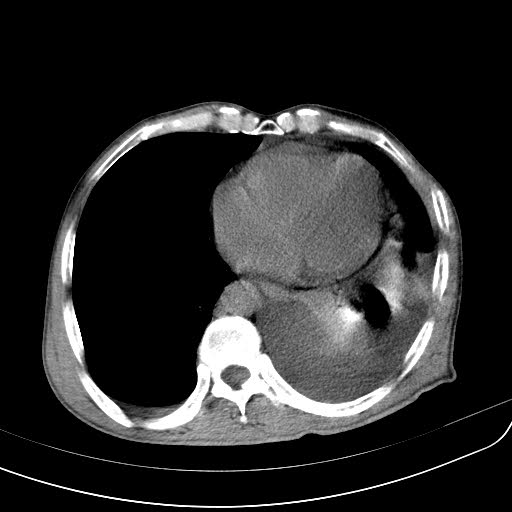

CT51165:男性 62Y 发现血尿一个星期左右;

小肠间质瘤?伴腹内胸腔及心包转移,并压迫或转移左肾导致肉眼血尿?建议肠镜

两侧胸腔积液,左侧尤著,左下肺膨胀不全,心包积液,左肾中上极见结节高密度影及类圆形低密度影,左肾内外似见混杂低密度,考虑左肾结石,左肾囊肿,左肾积液?建议增强,排除左肾占位。